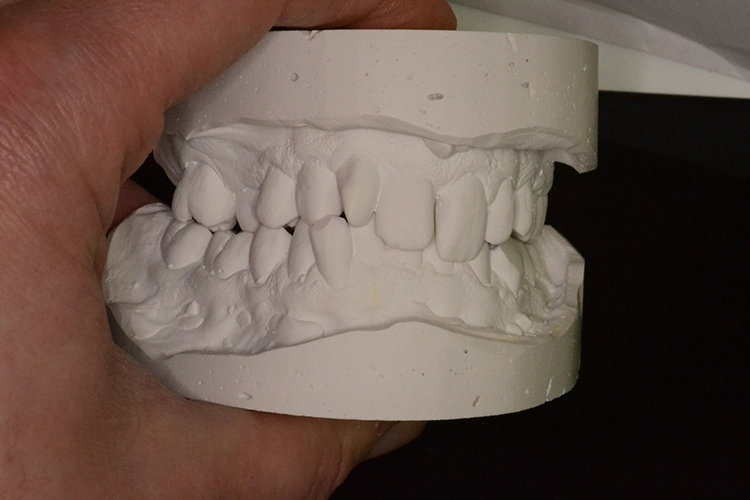

Bei diesem 49-jährigen, allgemeinanamnestisch unauffälligen Patienten liegen diverse ästhetisch störende Zahnstellungsanomalien vor, wobei Zahn 21 bei extremer Elongation frakturierte (Abb. 2a). Nach einer Übergangsversorgung mittels provisorischer Stiftkrone (Abb. 2b) entschied sich der Patient für eine Zahnentfernung bei gleichzeitiger Implantation. Im Ausgangs-DVT (Abb. 2c und d) zeigt sich im Cross-Sectional, wie weit der Processus alveolaris zurückliegt.